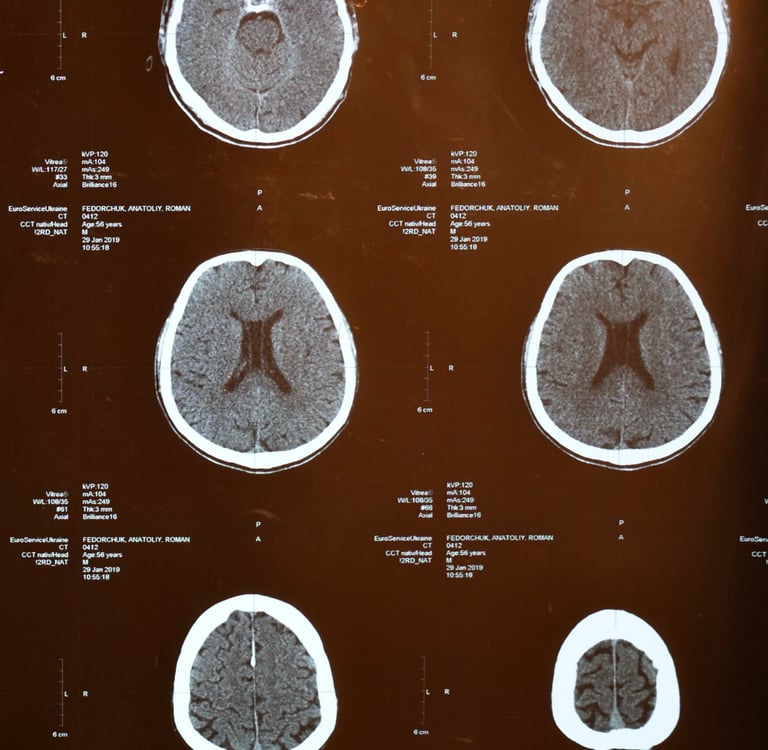

Stressors on the brain come in different shapes and sizes. Dr. Bredesen has identified over 30 possible stressors that could lead to cognitive decline.

They include:

glycotoxicity - persistantly elevated glucose levels in the blood, which causes glucose molecules to stick to proteins and lipids impairing their funtions.

chronic inflammation - our bodies natural defence against pathogens. erronously being turned on over a very long period of time.

Poor oxygenation - commonly occurs during sleep even in those who do not have obstructive sleep apnoea and those who do not snore.

vascular dysfuction - not getting enough oxygen to the brain

toxin exposure or an inability to clear toxins.

atrophy - a lack of hormonal support for the brain to maintain normal function.